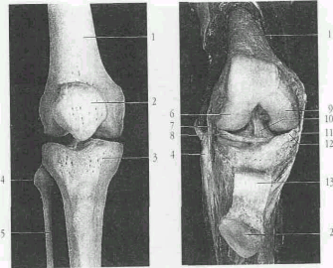

Рис.2 Костные элементы коленного сустава. Правый коленный сустав.

1 - бедренная кость;

2 - надколенник;

3 - большеберцовая кость;

4 - головка малоберцовой кости;

5 - малоберцовая кость;

6 - боковой (латеральный) мыщелок.;

7 - наружная боковая связка коленного сустава;

8 - латеральный мениск (межсуставной хрящ коленного сустава);

9 - медиальный мыщелок коленного сустава;

10 - передняя крестовидная связка;

11 - внутренняя боковая связка коленного сустава;

12 - внутренний мениск (промежуточный диск коленного сустава;

13 - связка надколенника.

Рис 4. Правый коленный сустав вид сзади

13 - связка надколенника;

14. - задняя крестообразная связка.